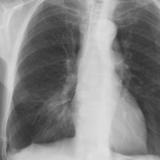

Case 2 PA